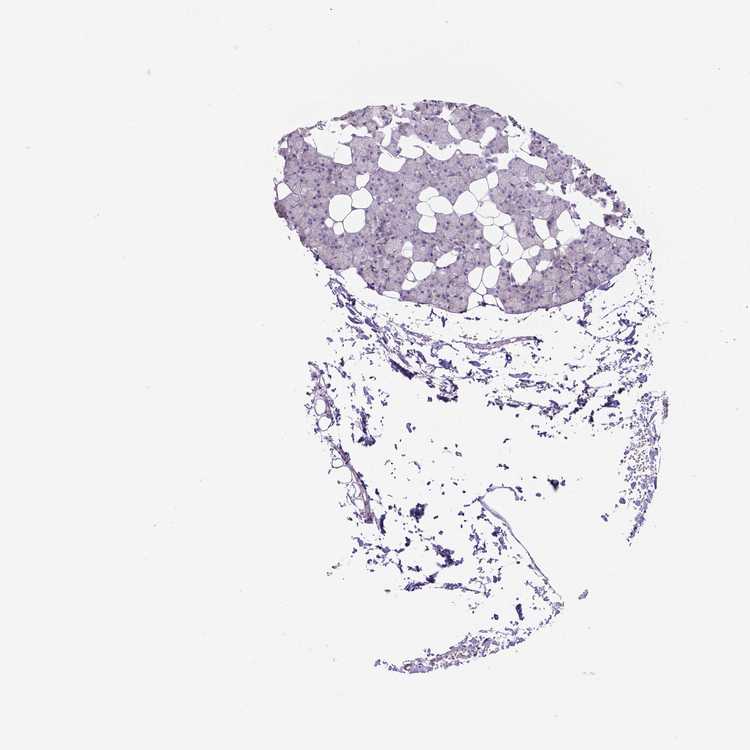

Male, age 60

Salivary gland sample 217

nTPM: 16

Cell types%

Glandular cells:

55

Ductal cells:

20

Adipocytes:

5

Endothelial cells:

Other cell types:

15